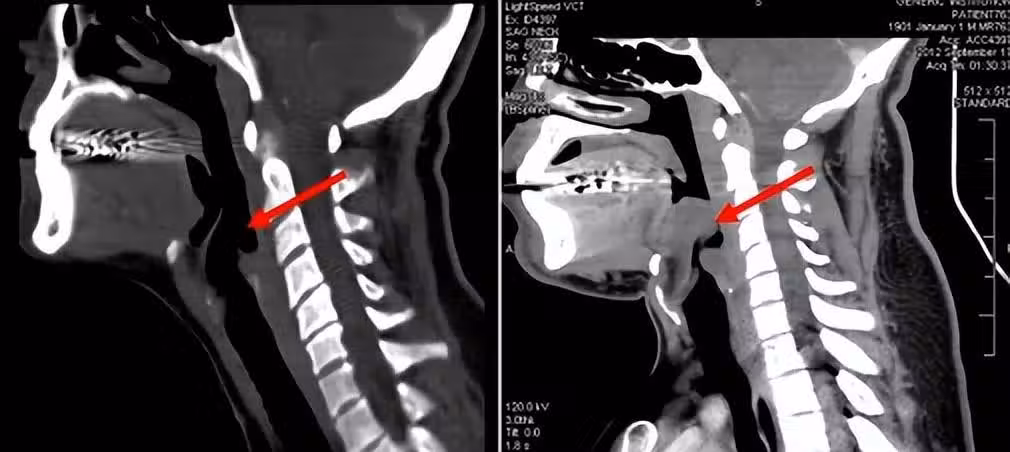

除了死亡率高以外,會厭炎還十分容易誤診,這也是這個病兇險的另一個原因。因為發病時,患者一開始的感受基本都是咽痛、吞咽困難,多數人會以為是扁桃體發炎、咽炎或者感冒,一般不會引起重視。